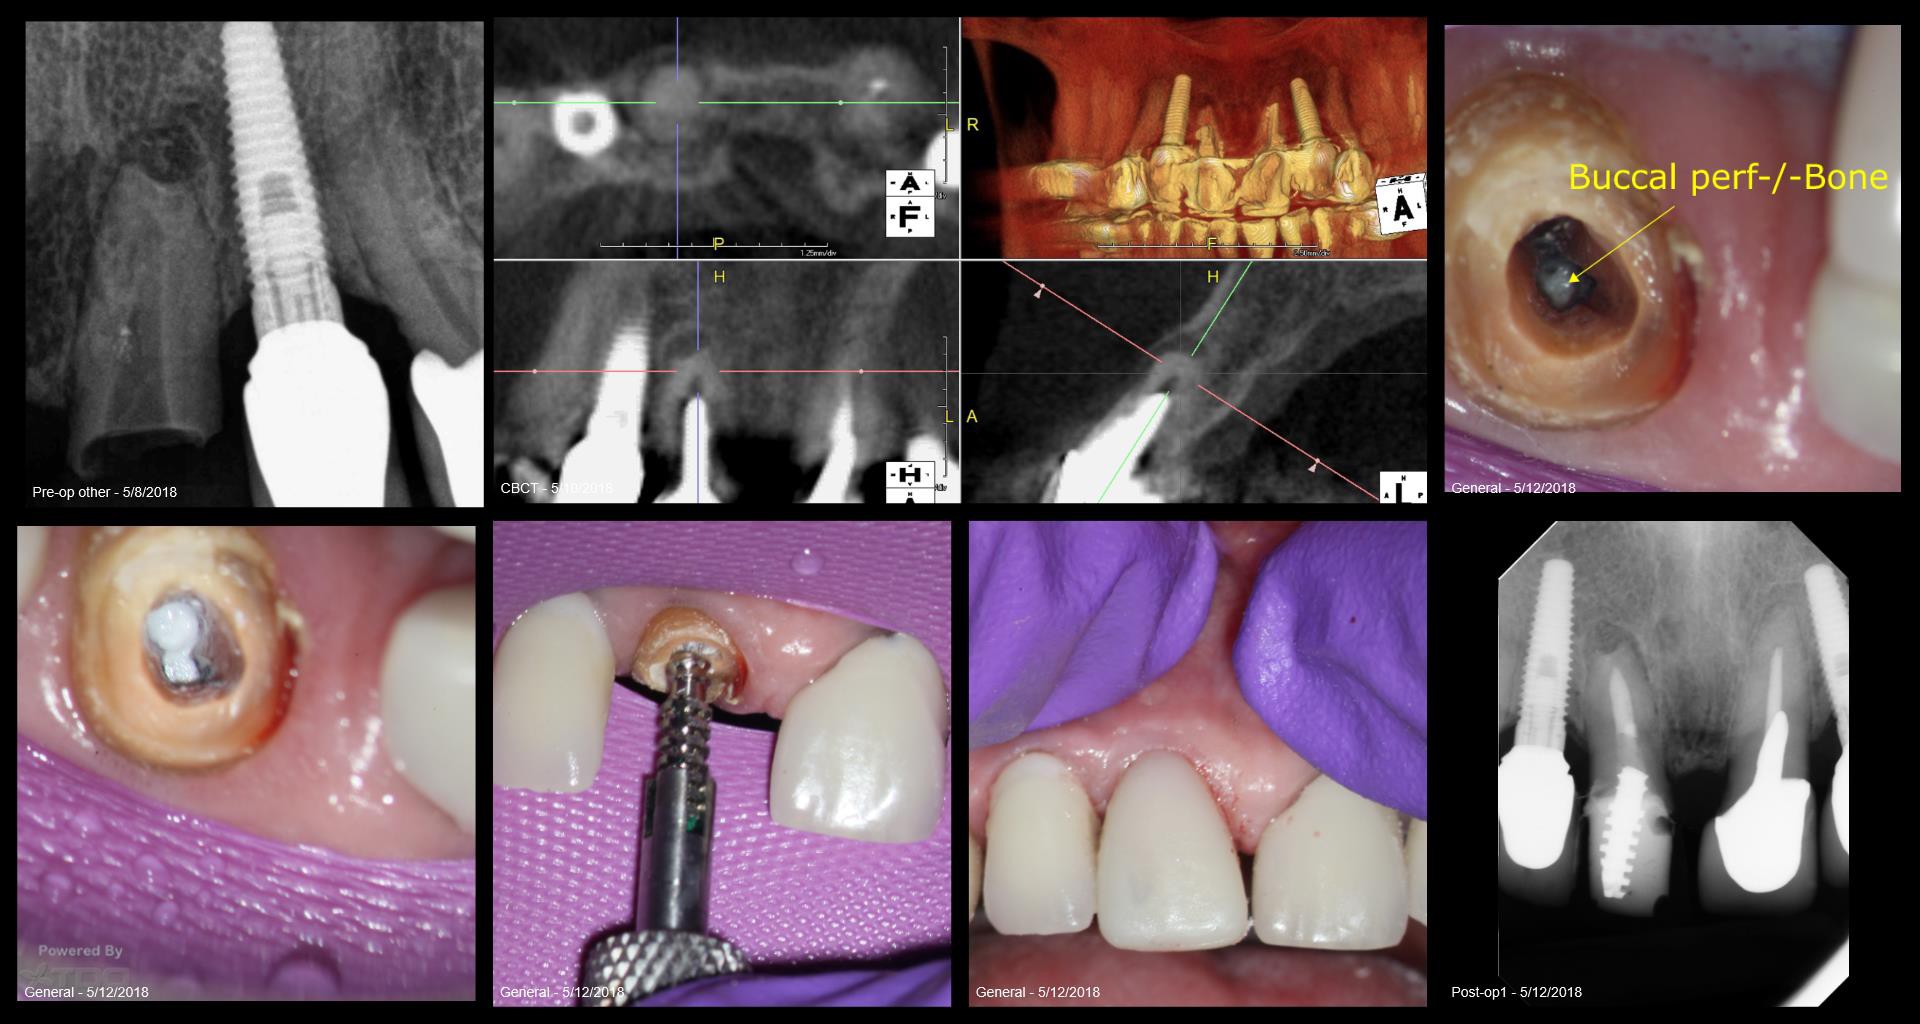

Poor Joy…..having to come in on her birthday… Patient here from Russia for treatment of ALS–in a wheelchair. Daughter a patient of mine—lead scientist on the MARS probe at Cal Tech. Just wants to be functional and to minimize costs if possible. Patient is 78. Tried to talk about a 6-12 implant supported bridge…..no go. SINUS TRACT mid root. She comes in today with the post/crown in her hand—the post had perforated the buccal aspect of the root. Tried to do mthe best I could. BCS sealer in the perf and RCT. Had to cut the Flexipost off to get it to have any purchase at all. Got some good retention,,,I think. Filled a temp crown with Luxicore. Couldn’t do this without Joy for shur….. gbc